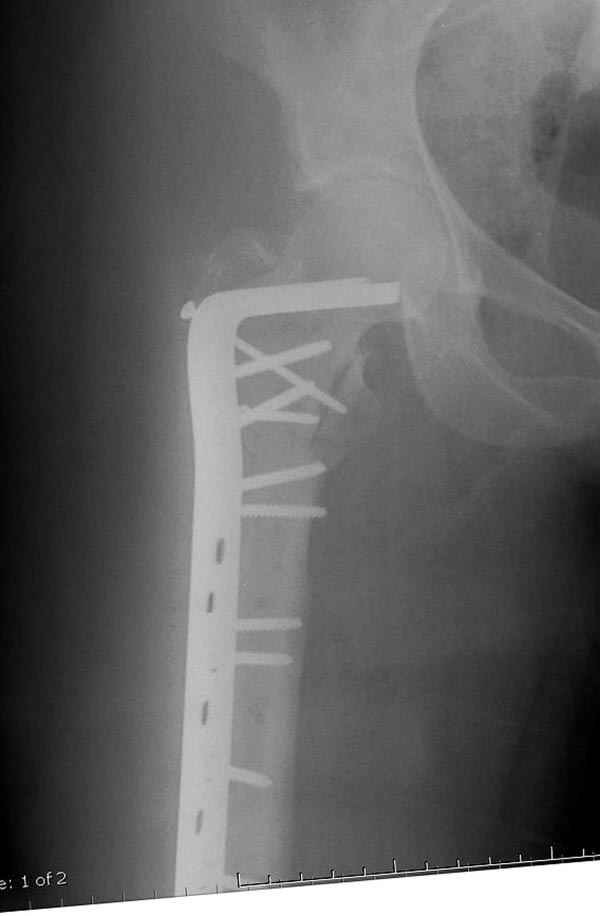

Второй случай тоже репозиция из малого доступа, больному 19 лет, множественные огнестрельные повреждениия конечностей, живота и черепа, правая конечность холодная, без пульсации. Ортопедический диагноз: огнестрельный перелом правого бедра. При срочной ангиографии повреждения сосудов не подтвердилось, конечность из-за ургентности состояния больного зафиксирована временным наружным фиксатором и больной оставлен на операционном столе для срочной лапаротомии хирургической службой.

Больной долго оставался нестабильным, только на 14 день удалось заменить на антеградный интромедуллярный штифт TFN (trochanteric femoral nail) SmithNephew. После неудачной попытки закрытой репозиции, несмотря на использование "joystick", проксимальный стержень от

наружного фиксатора, (перелом начал срастаться) репозицию провели из малого доступа, затем остальные этапы операции.

Случай был представлен из-за того, что больного оперировали после наружной фиксации и был риск инфекцирования через места проведения стержней (на снимках), прошло больше 3 месяцев, выписан из амбулаторной службы из-за отсутсвия надобности дальнейшего наблюдения.